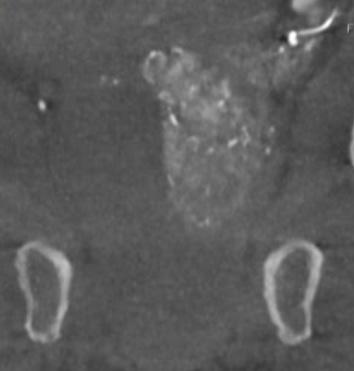

The incidence of lung cancer has increased considerably in the last few decades with the lung as the most common site of metastatic involvement. Despite the improvements in the diagnosis and treatment for malignant lung tumours, the prognosis of the patients is still unsatisfactory.1 Currently, locoregional chemotherapeutic techniques such as transpulmonary chemoembolization (TPCE) for the treatment of lung malignancies have gained increasing importance. The purpose of this retrospective study was to evaluate local tumour response and patient survival after the treatment of pulmonary metastases using TPCE as a palliative treatment method.

In TPCE, a 5 French (Fr) endovascular sheath and 5Fr headhunter catheter are routinely placed transfemorally under fluoroscopy until the pulmonary artery and subsequently the tumourfeeding segmental pulmonary branch are reached. A balloon catheter (up to 7mm in diameter) is optionally placed for better results.2 This selective pulmonary artery catheterisation results in a blockage of the arterial supply to the tumour tissue, resulting in regional ischaemic necrosis in the target tumour tissues while reducing damage to the surrounding normal lung parenchyma. Thereafter, mitomycin

and gemcitabine as chemotherapeutic agents are administered in combination with an embolization of lipiodol and microspheres. This extends the storage time of the injected cytostatics in the tumours and reduces the outflow into

the circulatory system.3 Consequently, the frequency and severity of systemic effects are limited. Other occlusion materials used are coils, polyvinyl alcohol, degradable starch microspheres, and gelatin sponges.

In our study, 223 patients (138 women, 85 men; mean age: 59.3±11.9 years) with unresectable lung metastases and/or not responding to systemic chemotherapy received repetitive TPCE (mean number of sessions 4.7±3.7) between January 1990 and May 2021. Patients had predominant lung metastases and in most cases with bilateral lung involvement. Origin of the metastases were either colorectal carcinoma (n=139) or breast cancer (n=84). Tumour-supplying vessels were catheterised selectively in order to apply chemotherapeutic agents locally, combined with lipiodol and microspheres. The response was assessed according to the revised RECIST criteria.

Of the evaluated 183 cases, partial response was achieved in 4.9% (n=9), stable disease in 62.3% (n=114), and progressive disease in 32.8% (n=60) of the patients. Mean and median overall survival time were 23.5 and 14 months, respectively.

TPCE can be used as a palliative treatment in unresectable lung malignancies to reduce the tumour burden or to achieve local tumour control,4 or as a neoadjuvant or curative treatment option combined with thermal ablation such as radiofrequency ablation (RFA) and microwave ablation (MWA) (Figure 1).5,6

A multicentre study may include a larger population of patients and combine expertise from different institutes. Although TPCE has the potential to improve local tumour control and to prolong survival, randomised controlled trials are still needed.